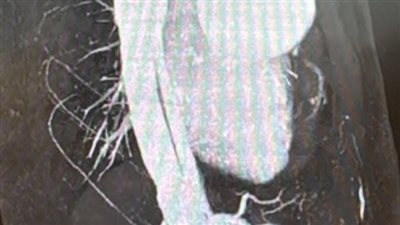

تمكن فريق الأشعة بمستشفى منوف العام، بقيادة الدكتور حاتم طاحون مدير المستشفى، من تحقيق إنجاز طبي جديد، حيث نجح في تشخيص حالة تمزق بالشريان الأورطي (Aortic Dissection) بدقة عالية